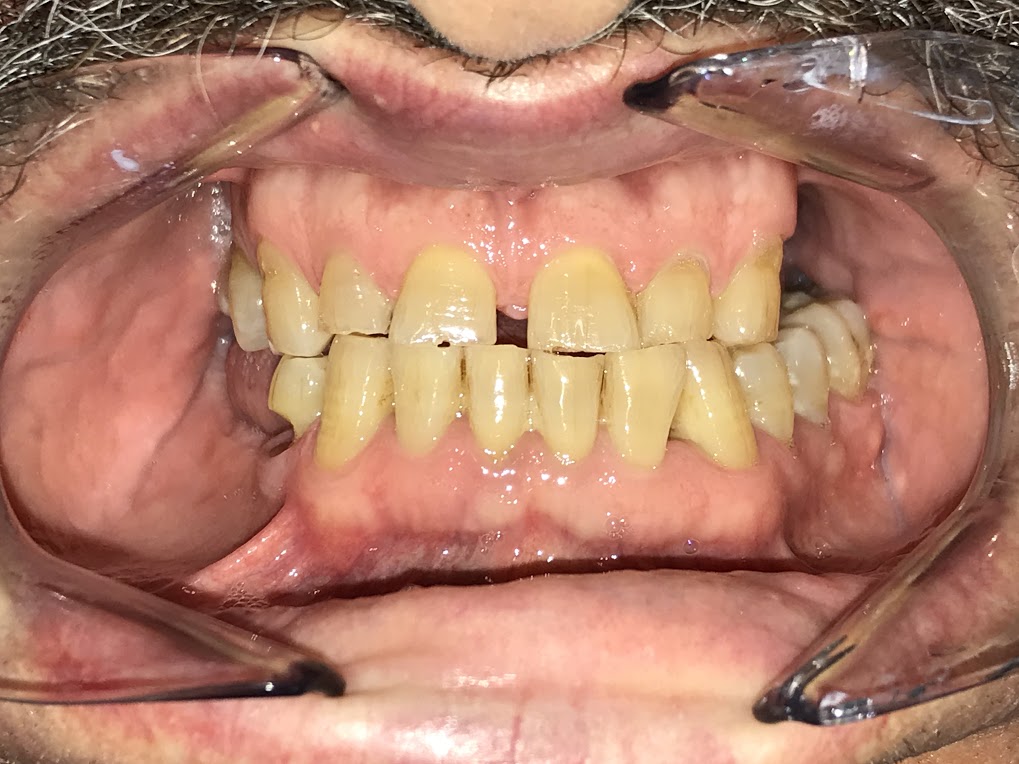

Acude al máster paciente varón de 58 años, sin antecedentes médicos de interés por dolor en zona inferior derecha.

A la exploración observamos una lesión cervical no cariosa en el diente 44, de tipo abfracción, que parece ser la responsable del dolor. A las pruebas pertinentes obtenemos una sensibilidad aumentada, percusión -, palpación -, sondaje fisiológico y ausencia de movilidad.